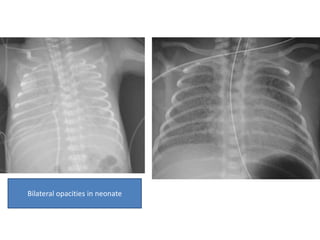

• Plain radiograph

• low lung volumes

• diffuse, bilateral and symmetrical granular opacities

• bell-shaped thorax

• air bronchograms

Bilateral opacities in neonate